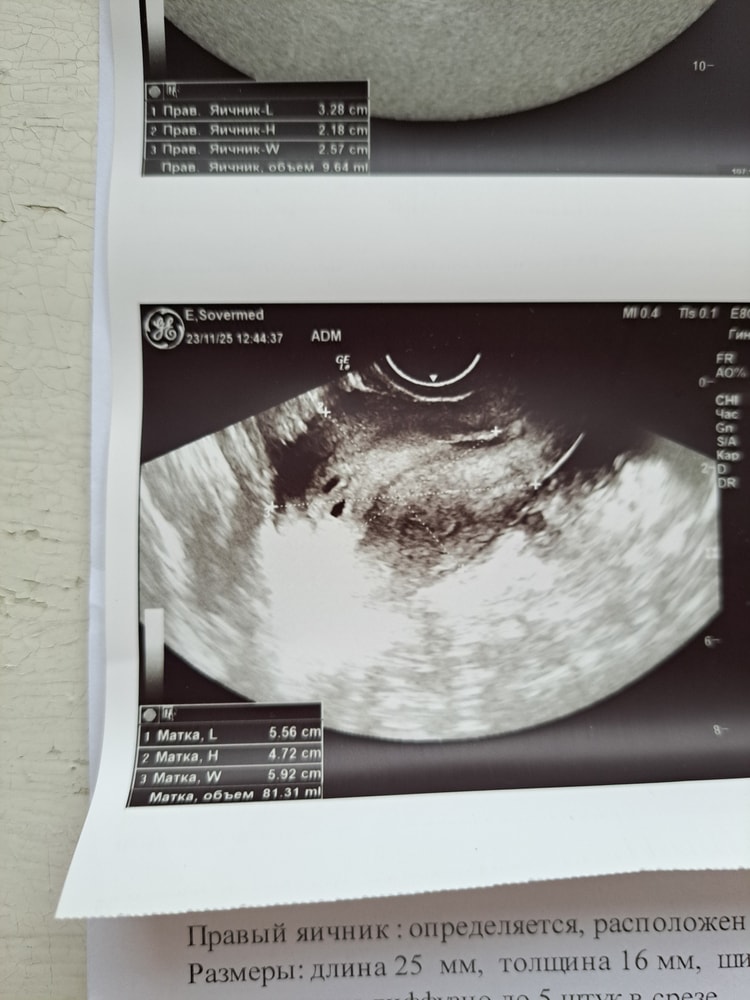

УЗИ, КТГ, доплер, скрининг, ХГЧ и другие анализыДобрый день! Сегодня сходила на узи. (Фото узи в комментариях) Ровно 5 недель по мес. (Знаю, что рано). Врач на узи увидела 2 плодных яйца, но одно желтое тело 16 мм.

Такое возможно? Очень смущает, что всего 1 желтое тело, хотя в таком случае ведь должно быть 2? Может у кого-то было так-же, что у вас в итоге, 1 или двойня?

Последняя динамика хгч за 48 ч. - 967мМе/мл, затем 3602мМе/мл.